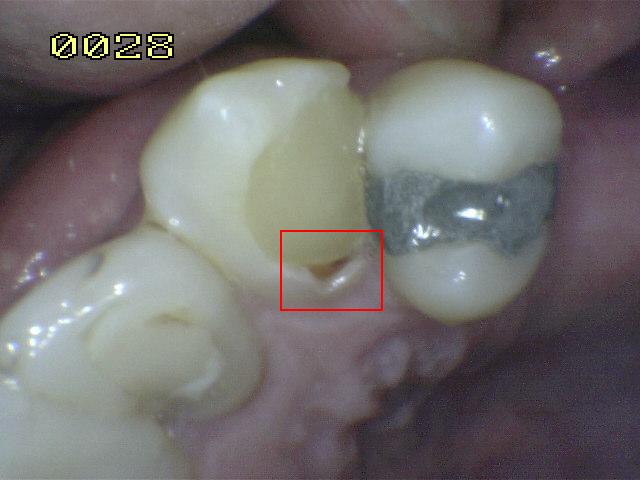

Código 3

(Caries Moderada): Ruptura

localizada del esmalte debido a caries sin dentina visible.

-

Cavidad en el margen de la

restauración/sellante menor a 0,5mm, además de tener una

opacidad o una pigmentación relacionada con

desmineralización que no es compatible con la apariencia

clínica de esmalte sano o con una sombra subyacente en

la dentina.

Utilizar una

sonda con

presión suave. para identificar la pérdida de

anatómica.

Opacidad o decoloración consistente con

desmineralización.